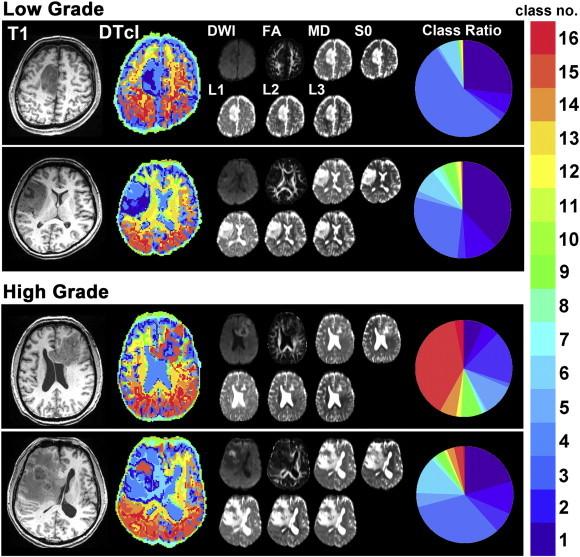

Gliomas are the most common intra-axial primary brain tumour; therefore, predicting glioma grade would influence therapeutic strategies. Although several methods based on single or multiple parameters from diagnostic images exist, a definitive method for pre-operatively determining glioma grade remains unknown. We aimed to develop an unsupervised method using multiple parameters from pre-operative diffusion tensor images for obtaining a clustered image that could enable visual grading of gliomas. Fourteen patients with low-grade gliomas and 19 with high-grade gliomas underwent diffusion tensor imaging and three-dimensional T1-weighted magnetic resonance imaging before tumour resection. Seven features including diffusion-weighted imaging, fractional anisotropy, first eigenvalue, second eigenvalue, third eigenvalue, mean diffusivity and raw T2 signal with no diffusion weighting, were extracted as multiple parameters from diffusion tensor imaging. We developed a two-level clustering approach for a self-organizing map followed by the K-means algorithm to enable unsupervised clustering of a large number of input vectors with the seven features for the whole brain. The vectors were grouped by the self-organizing map as protoclusters, which were classified into the smaller number of clusters by K-means to make a voxel-based diffusion tensor-based clustered image. Furthermore, we also determined if the diffusion tensor-based clustered image was really helpful for predicting pre-operative glioma grade in a supervised manner. The ratio of each class in the diffusion tensor-based clustered images was calculated from the regions of interest manually traced on the diffusion tensor imaging space, and the common logarithmic ratio scales were calculated. We then applied support vector machine as a classifier for distinguishing between low- and high-grade gliomas. Consequently, the sensitivity, specificity, accuracy and area under the curve of receiver operating characteristic curves from the 16-class diffusion tensor-based clustered images that showed the best performance for differentiating high- and low-grade gliomas were 0.848, 0.745, 0.804 and 0.912, respectively. Furthermore, the log-ratio value of each class of the 16-class diffusion tensor-based clustered images was compared between low- and high-grade gliomas, and the log-ratio values of classes 14, 15 and 16 in the high-grade gliomas were significantly higher than those in the low-grade gliomas (p < 0.005, p < 0.001 and p < 0.001, respectively). These classes comprised different patterns of the seven diffusion tensor imaging-based parameters. The results suggest that the multiple diffusion tensor imaging-based parameters from the voxel-based diffusion tensor-based clustered images can help differentiate between low- and high-grade gliomas.